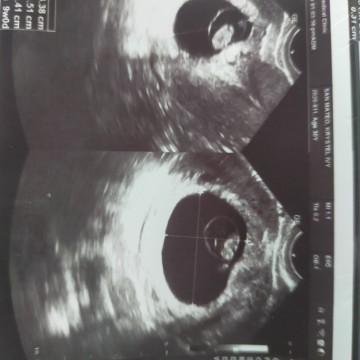

hi mga mommy, july 5 edd ko 16 weeks now pero halos wala padin movement ni baby n nnrmdman.. Same din po b sainyo? As per ob ko ky heartbeat nman baby ko mlkas daw nmn kaso still worried po last pregnancy ko 9years ago p and medyo malikot xa kayak medyo worried tlg ko..